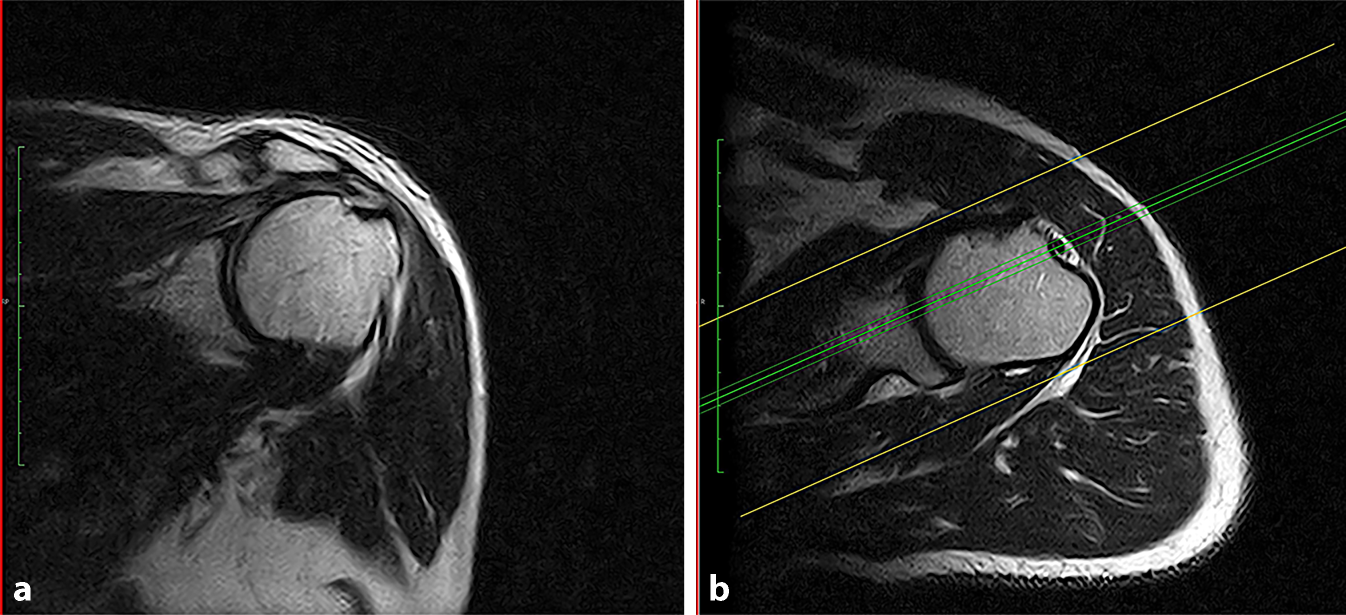

Dynamische Bildgebung der Schulter in der funktionellen Magnetresonanztomographie

Primäres Ziel dieser Studie war die Entwicklung und Evaluation einer Messmethode der anterioposterioren (AP-)Translat...